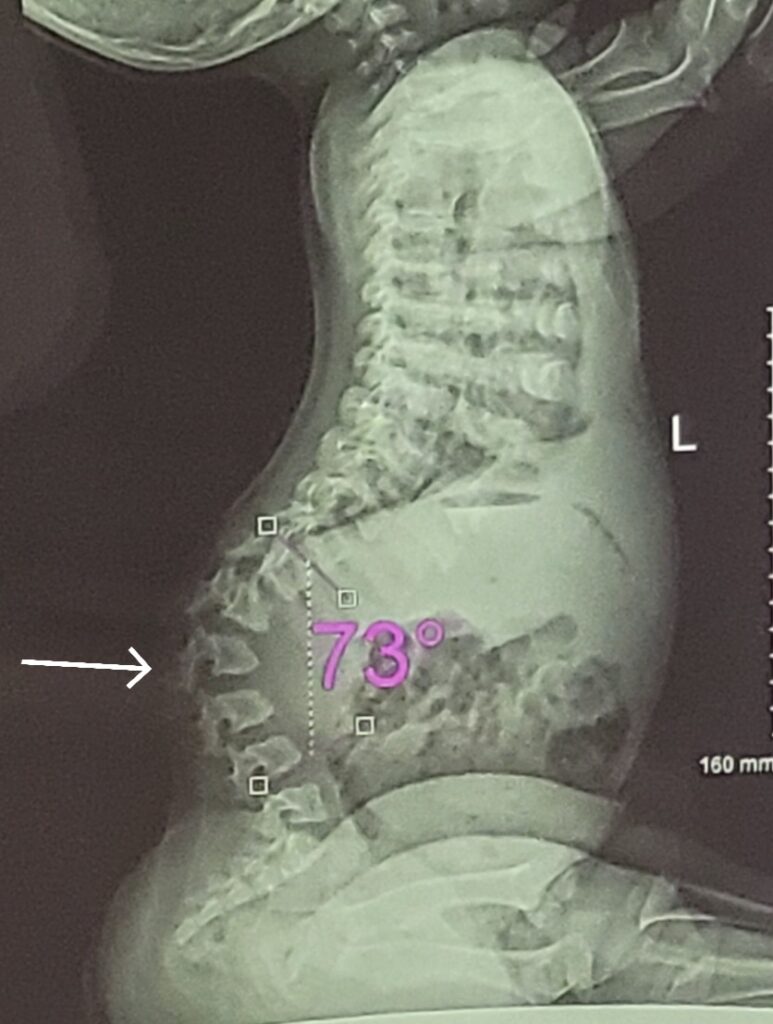

後弯は背骨のレントゲンを撮って整形外科医に診断してもらいます。

診断をする際、Cobb角というのを測定して弯曲している角度を見ます。このCobb角の角度によって軽症~重症を診断します。

15~30度 正常範囲内

30~45度 予備軍または軽度

45~60度 中度

60~80度 重症

はじめに紹介したこの写真、実はモーリーの実際のレントゲンです。Cobb角は73度と重症。また、医師が懸念点にあげたのが骨の変形です。

白い→の後弯部をズームした写真がこちら。※少し画像が粗くてすみません。

脊椎は本来、写真の上にあるイラストのように四角っぽい形に羽が生えたような形をしているのが正常なのですがモーリーの場合は写真の下にあるイラストのように後弯によって脊椎同士がつぶして傷つけあってしまっています。そのため→の脊椎とその上下の脊椎の形が変形してつぶれた四角形や削れ過ぎて三角形に近い形になってきているのがわかると思います。